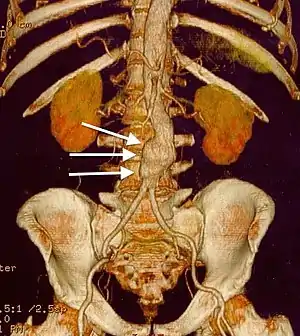

CT reconstruction image of an abdominal aortic aneurysm (white arrows)